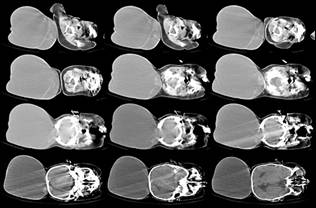

Image

3: CT scan brain (bone window) showing large defect in the occipital bone with

sclerosed margins.